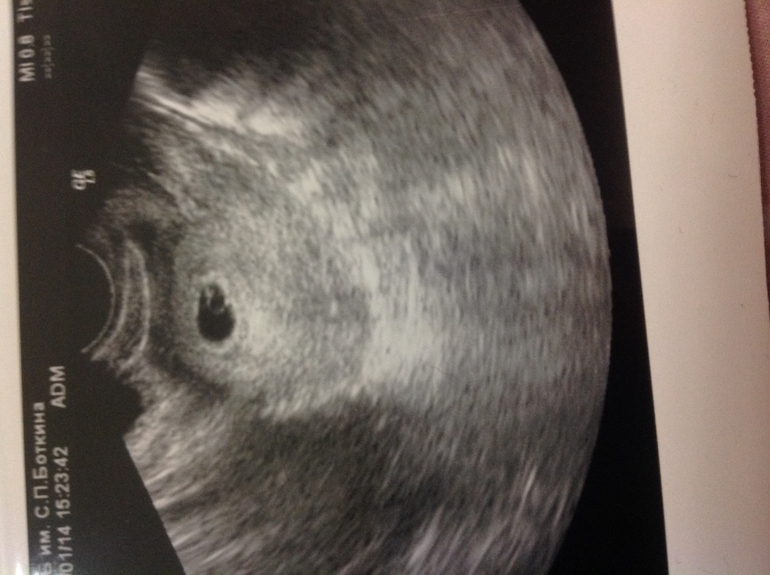

И так нам уже 4-5 недель !!меня ус покоили что пока ничего не слышно так как маленький срок,через неделю уже будет все стучать))сказали что тонуса матки нет,что все хорошо)теперь я спокойный удав)оказывается что это все поздняя овулька ,поэтому не стоит переживать!)сказали сдать кровь с утра чтоб все было в норме )и можно уже на учет вставать,но пока не буду спешить где-нибудь в феврале встану когда уже скрининг надо будет делать!!) девочки скажите на что самое главное надо обратить внимание в первом триместре??)